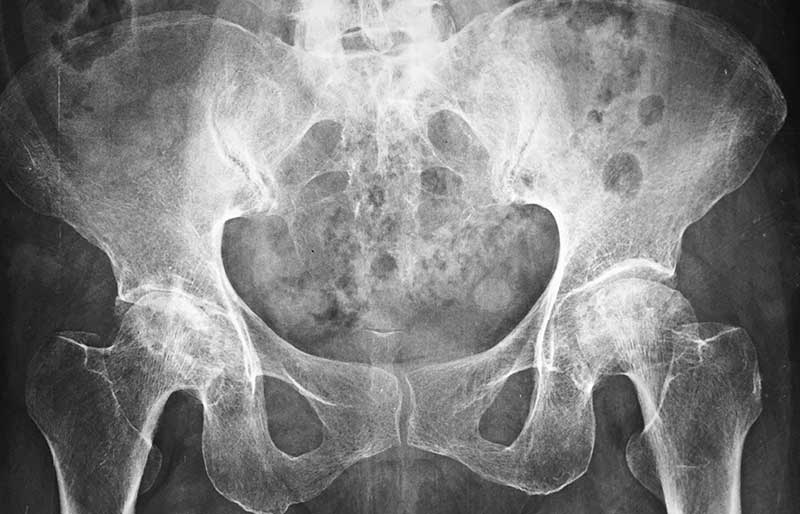

Operasi penggantian sendi panggul adalah suatu operasi untuk mengganti sendi panggul yang rusak dengan sendi buatan yang disebut prosthesis. Penyebab utama kerusakan sendi panggul adalah osteoartritis (baca penjelasan tentang “Osteoartritis”) dan sendi panggul adalah sendi terbanyak kedua setelah lutut yang terserang penyakit ini.

Operasi penggantian sendi panggul merupakan pengobatan terbaik untuk osteoartritis panggul stadium yang berat. Ada empat tujuan operasi ini, yaitu menghilangkan rasa sakit sendi yang telah rusak, memperbaiki lingkup gerak sendi yang sebelumnya kaku dan terbatas, mengembalikan kemampuan penderita melakukan aktivitas harian tanpa rasa sakit, dan meningkatkan kualitas hidup sehingga penderita kerusakan sendi dapat menjalani hidup secara aktif bebas dari nyeri sendi panggul.